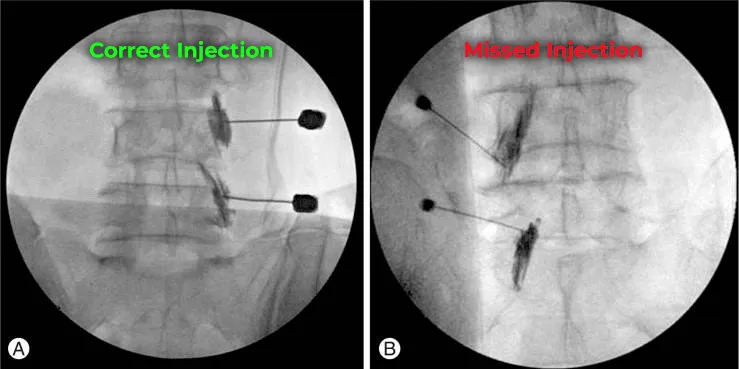

X-ray images showing correct and missed spinal injections labeled in green and red.

Many Injections Miss the Joint Entirely

Research has demonstrated that a significant percentage of facet joint injections fail to place medication accurately within the joint capsule, even when fluoroscopic (X-ray) guidance is used. The medication disperses into surrounding tissue with no therapeutic benefit.